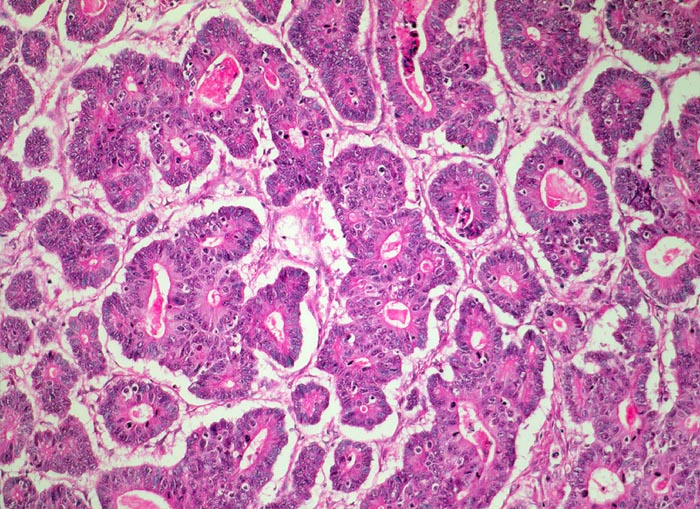

Morphologische Merkmale:

• Am unteren Ende des Präparates Antrummukosa mit mässiggradiger chronischer, geringgradig aktiver Gastritis und ausgedehnter intestinaler Metaplasie (Becherzellen).

• Weiter oben Invasion der Magenschleimhaut durch ein teils solides, teils drüsenbildendes Adenokarzinom mit stark atypischen Tumorzellen.

• Fokale Erosion des Karzinoms bedeckt von fibrinoleukozytärer Membran.

• Tumorinfiltration der Submukosa an der oberen Präparathälfte.

• Der invasive Karzinomanteil zeigt teilweise muzinöse Differenzierung (teils siegelringzellige Tumorzellen schwimmen in extrazellulären Schleimseen).

• Tumorfreie Lamina muscularis propria.